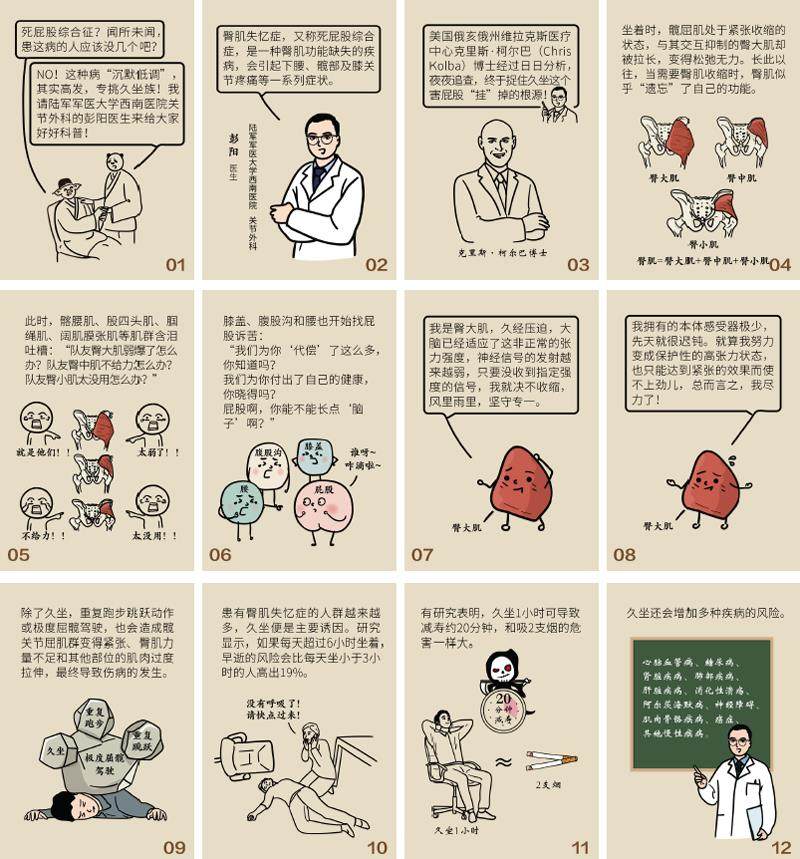

防病强身 | 久坐成伤,屁股遭殃

防病强身 | 久坐成伤,屁股遭殃